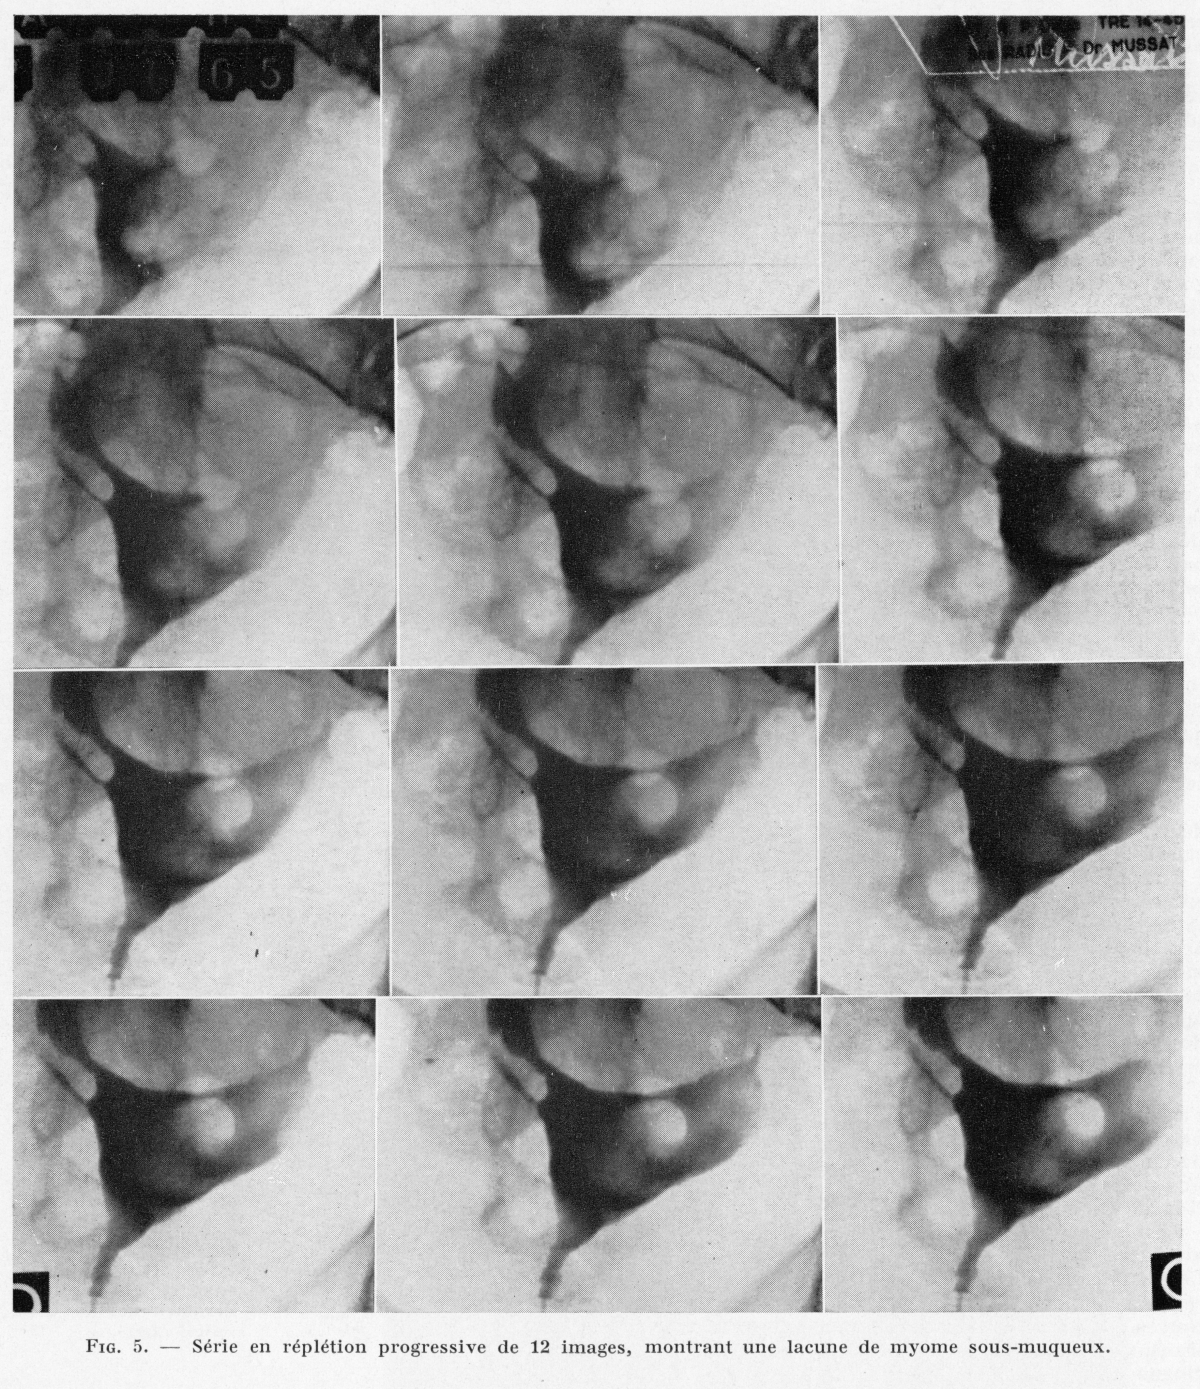

radio mussat